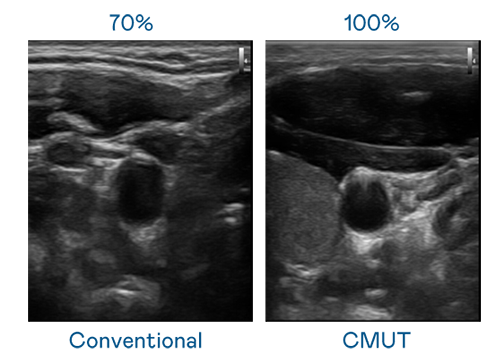

CMUT 技术是一种用电容式微机电元件来产生超音波讯号的技术。与传统 PZT 压电式技术相比,CMUT 频宽增加 30%,更宽频的超音波讯号让影像解析度大幅提升,是实现高影像品质医疗超音波扫描、促进精准医疗发展的关键技术。

大频宽带来超清晰影像

超音波影像的解析度高低,首先取决于探头能发出的讯号频宽。尊龙凯时官网 CMUT 可提供高清晰的超音波讯号,提供高频宽、高灵敏度、影像纹理细节更高的超音波影像,协助医护人员缩短影像判读时间及利用精准的医疗影像进行诊断。